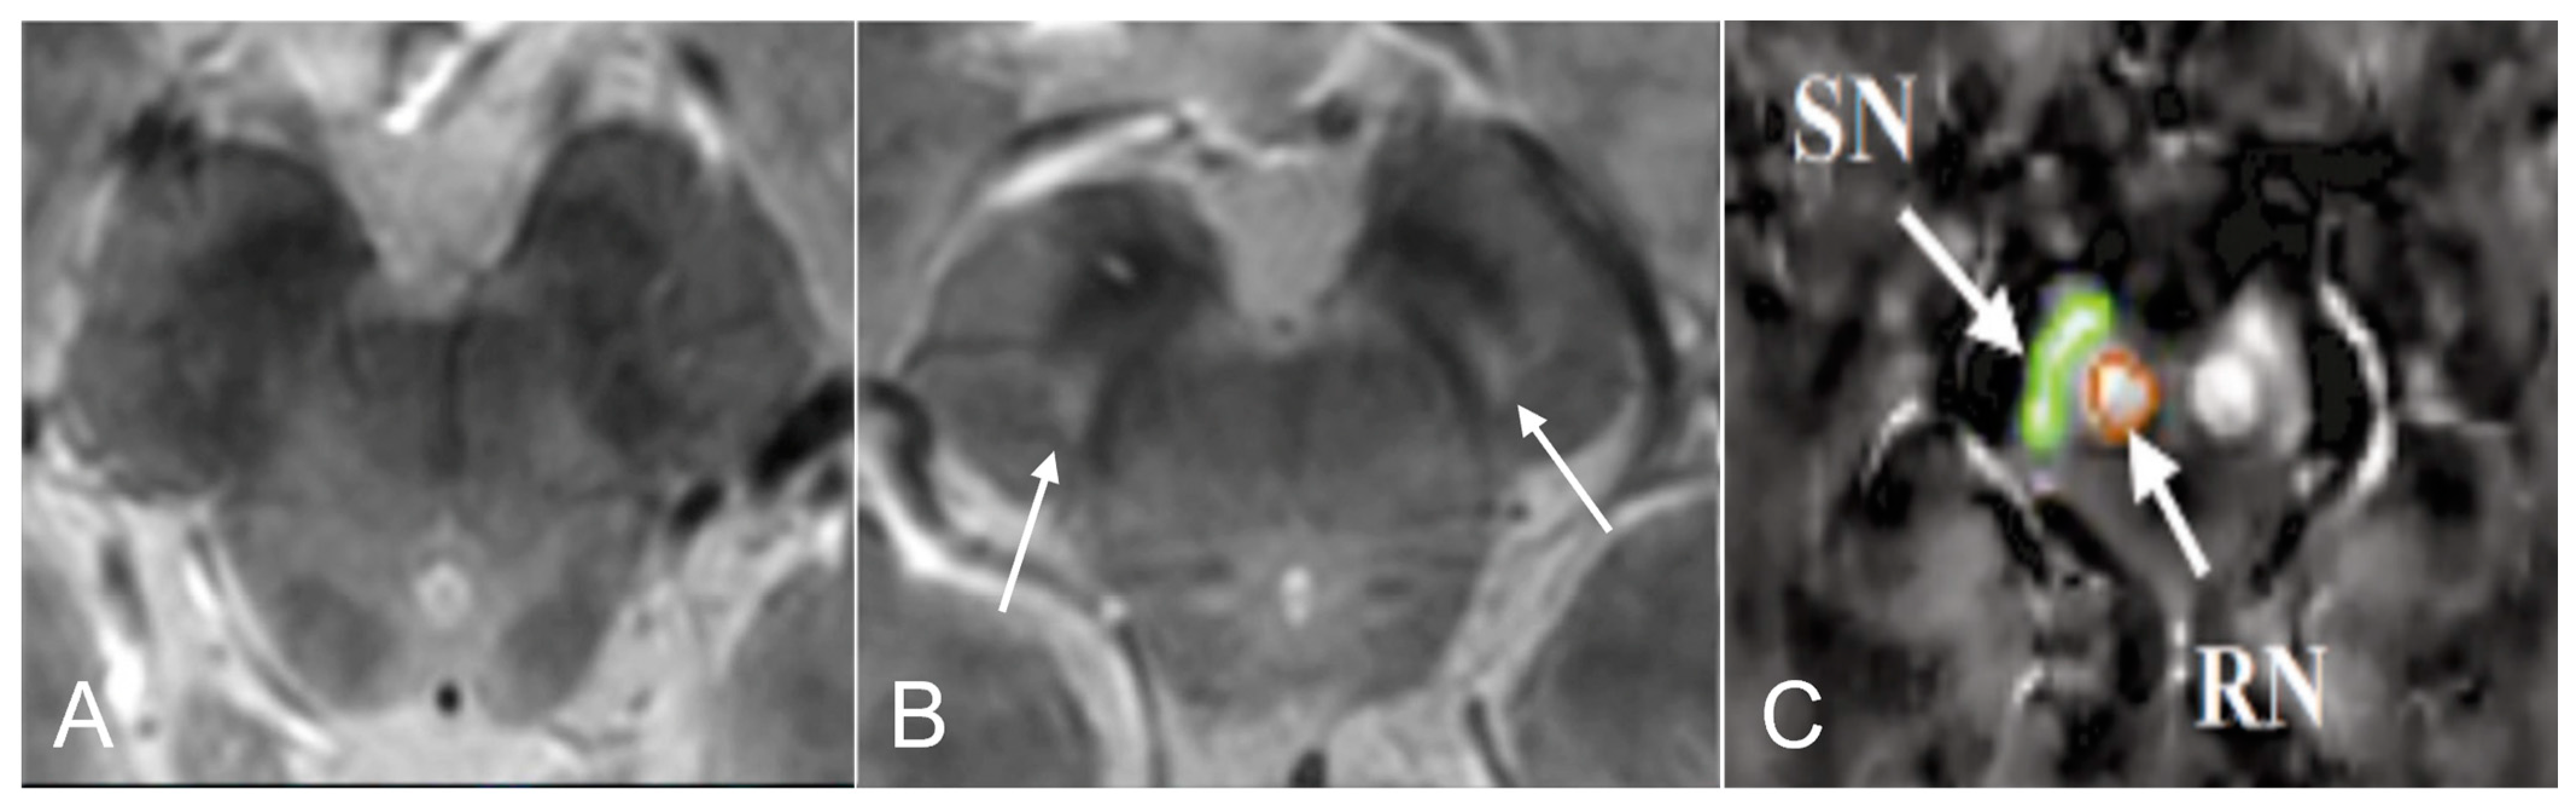

- Pyatigorskaya, N.; Gaurav, R.; Arnaldi, D.; Leu-Semenescu, S.; Yahia-Cherif, L.; Valabregue, R.; Vidailhet, M.; Arnulf, I.; Lehéricy, S. Magnetic Resonance Imaging Biomarkers to Assess Substantia Nigra Damage in Idiopathic Rapid Eye Movement Sleep Behavior Disorder. Sleep 2017, 40, zsx149. [Google Scholar] [CrossRef] [PubMed]

- Frosini, D.; Cosottini, M.; Donatelli, G.; Costagli, M.; Biagi, L.; Pacchetti, C.; Terzaghi, M.; Cortelli, P.; Arnaldi, D.; Bonanni, E.; et al. Seven tesla MRI of the substantia nigra in patients with rapid eye movement sleep behavior disorder. Park. Relat. Disord. 2017, 43, 105–109. [Google Scholar] [CrossRef]